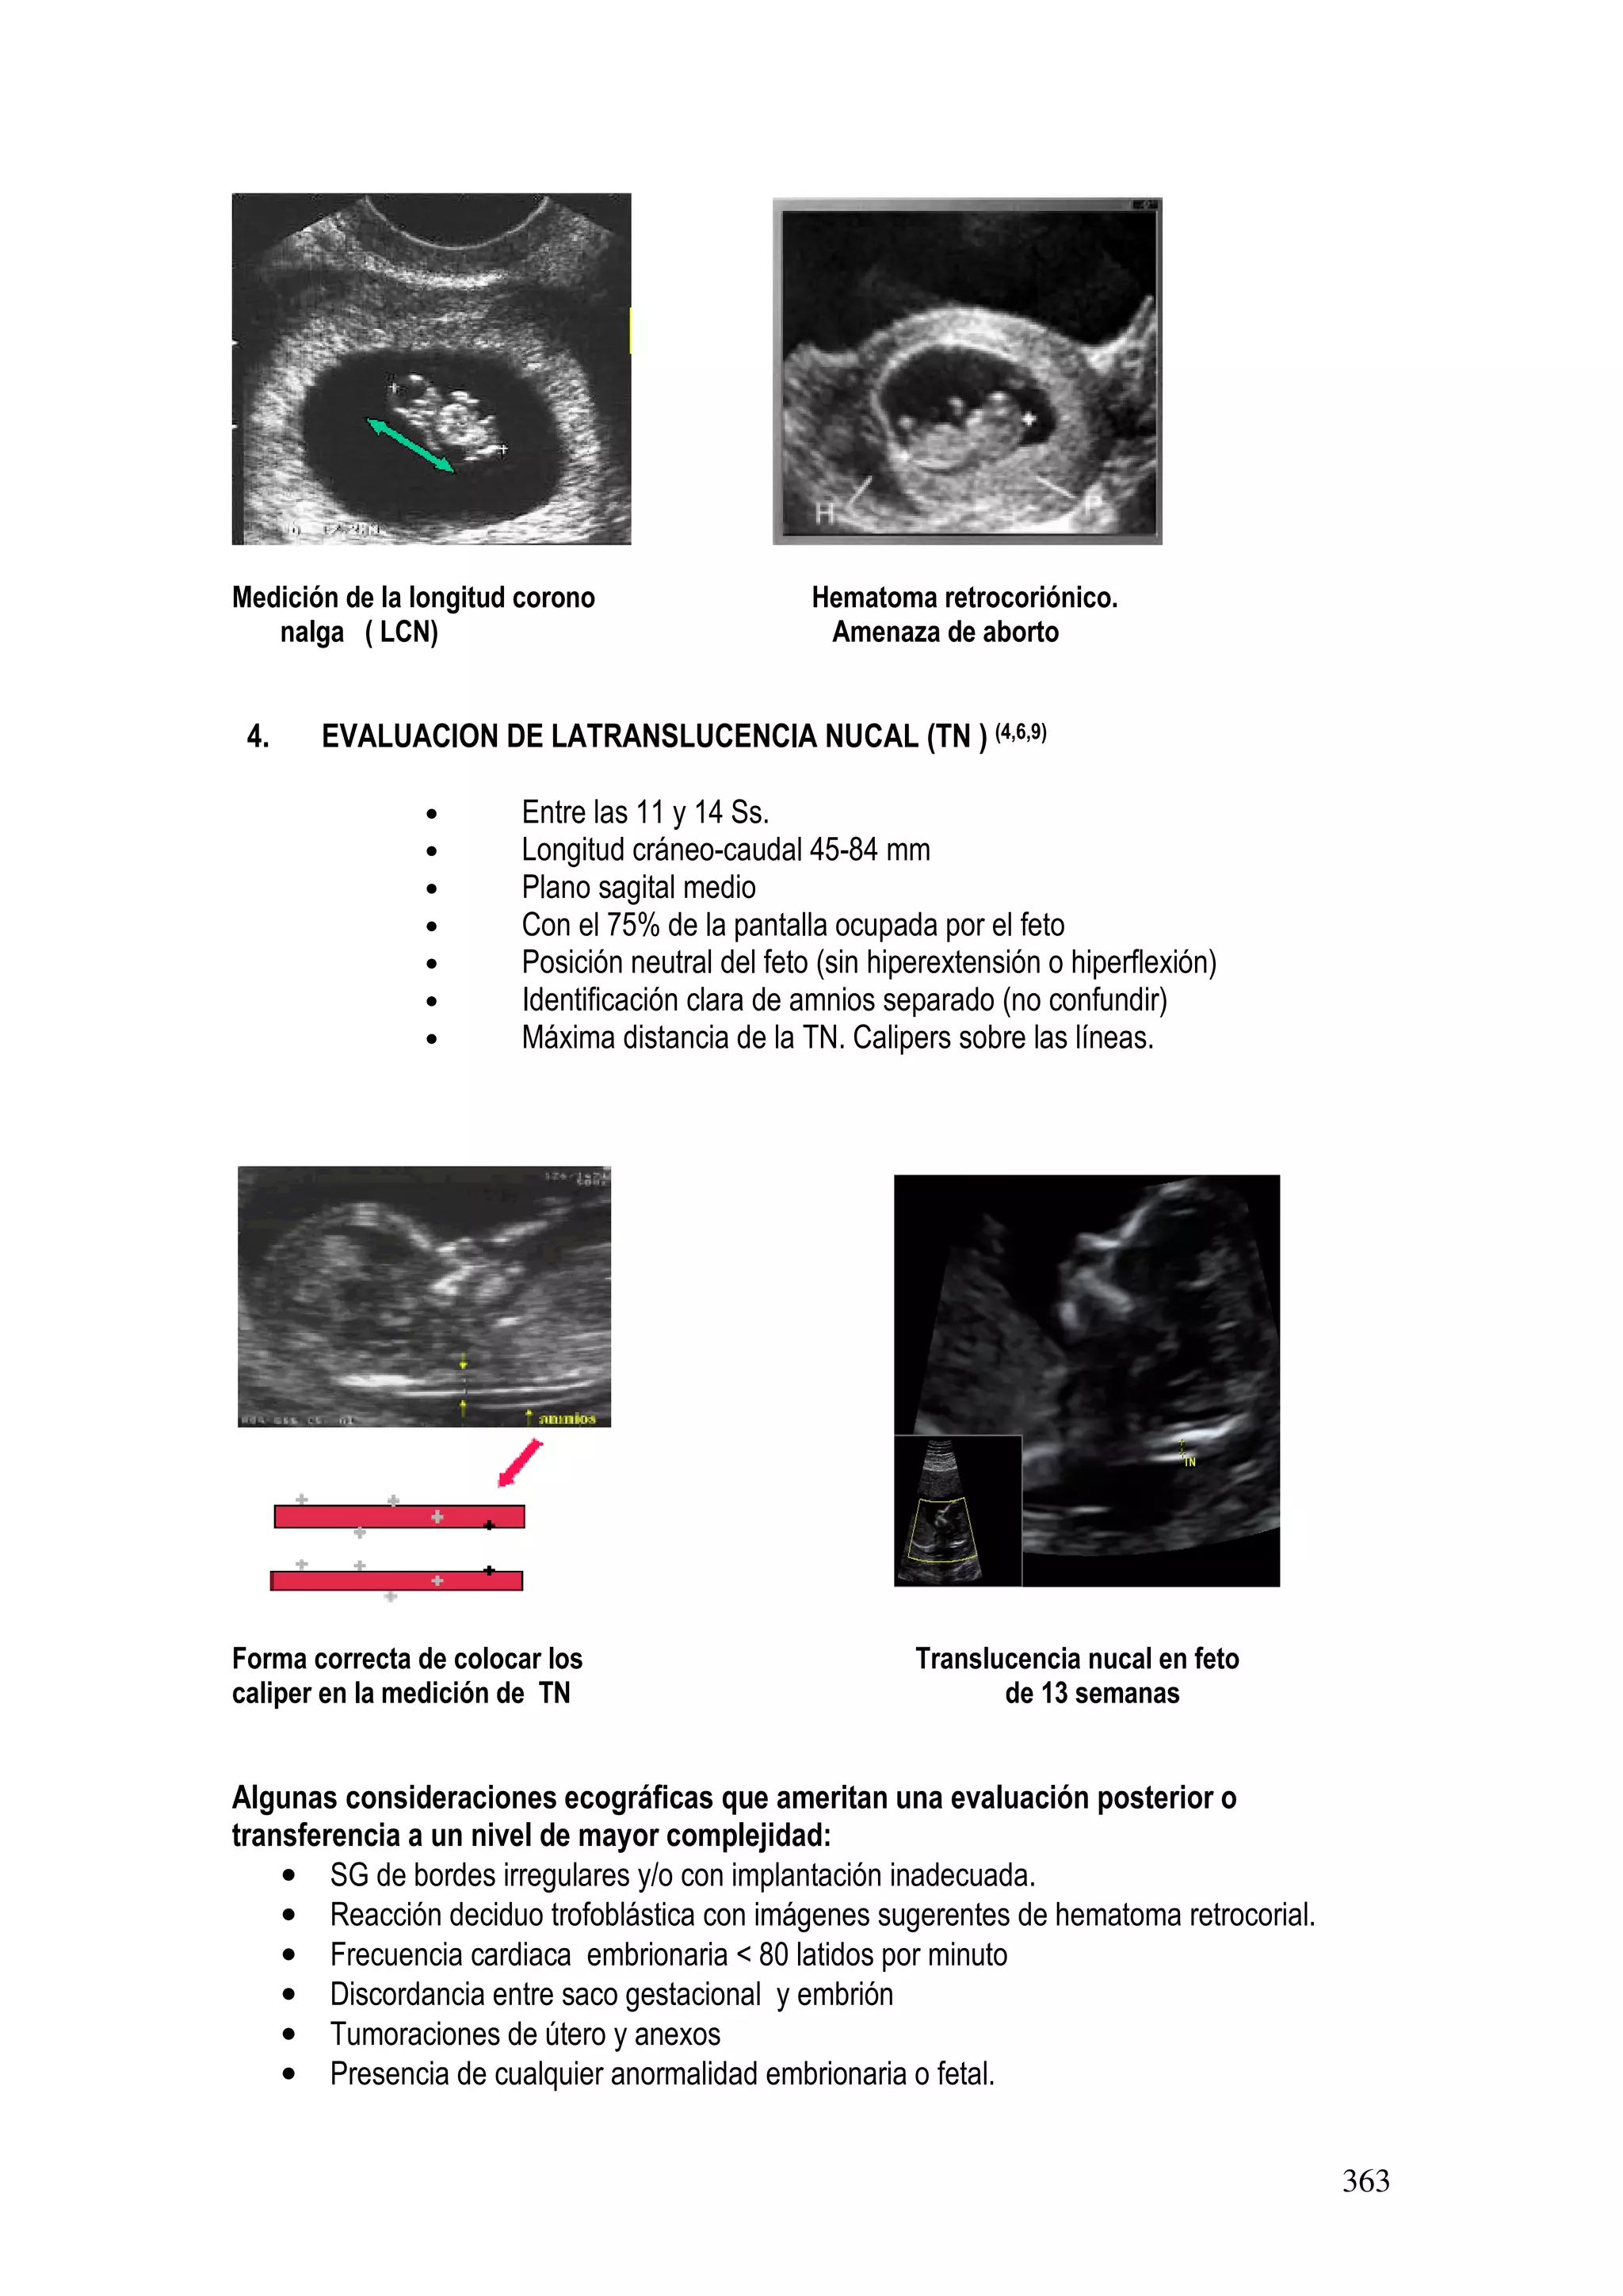

gelatina del cuello uterino las mismas que no han tenido aceptación y estudio adecuado.

Conducta obstétrica

Descartar rotura prematura de membranas.

Embarazos menores de 26 sem: ILA menor de 5 y peso fetal menor de 1000 gr

• Valoración por Genética, si existe malformación fetal proponer interrupción.

• No malformación fetal, se realiza hidratación materna con ClNa 0,9º/oo 3000 ml, en 24

horas, y se repetirá US a las 72 h, si persiste el Oligoamnios se discutirá en